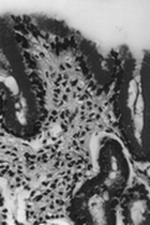

Երկրորդ աստիճանի ակտիվության գաստրիտի պայմաններում (18 կենսազննուկ) լորձաթաղանթը օջախային կամ տարածուն ծծանցված էր լիմֆոցիտներով, մակրոֆագերով, դիտվում էր գեղձային կառուցվածքների բազմաձևություն, թելակազմ շարակցական հյուսվածքի աճ, գեղձերի ապաճում և գերգոյացում (նկ. 3)։ Այսպիսի դեպքերում HP-ի քանակը տեսադաշտում հասնում էր 35-45-ի։

Նկ. 3. Խրոնիկական ատրոֆիկ գաստրիտ, գեղձերի ապաճում, ֆիբրոզ հյուսվածքի աճ։ Հեմատոքսիլին – Էոզին, X 100